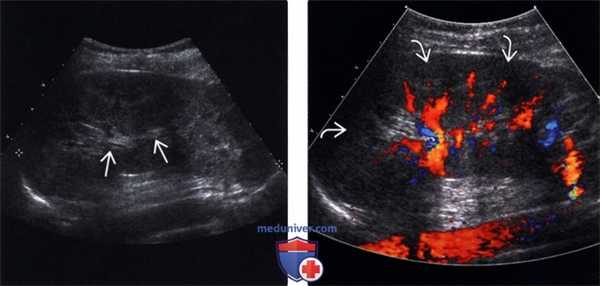

(Слева) УЗИ в режиме серой шкалы, сагиттальная плоскость сканирования: при остром геморрагическом пиелонефрите обнаружены клиновидные области повышенной эхогенности в нижнем полюсе и тонкий ободок прилежащей околопочечной жидкости.

(Справа) Энергетическая допплерография, сагиттальная плоскость сканирования: у данного пациента выявлено отсутствие потока в области пиелонефрита.